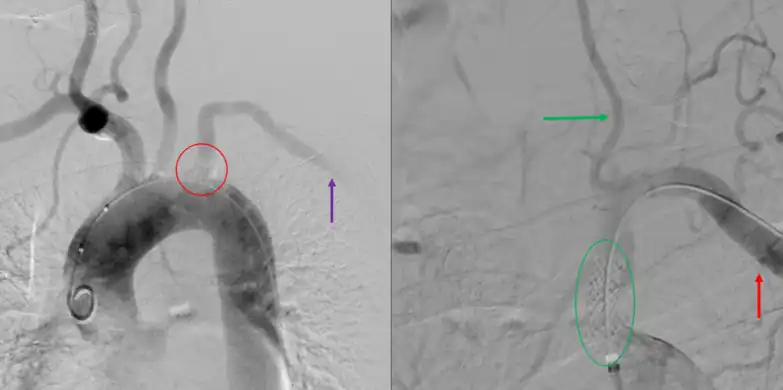

Angiogram of subclavian steal phenomenon before and after stent placement